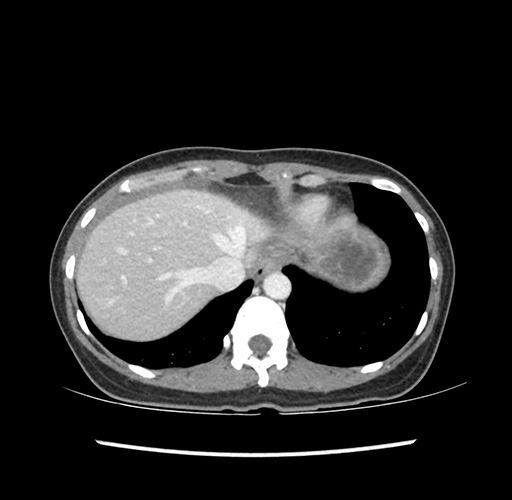

Imaging Analysis

Look through the patient's CT scan to identify any areas of concern for the necessary procedure.

Based on your CT findings, which issue(s) would give reason for "planned slowing down moment(s)" in this case?